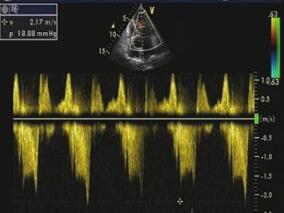

1小时条评论【一般情况】 男,45岁,汉族。 【主诉】 持续性胸痛1小时。 【病史摘要】 患者车祸后出现左侧胸部疼痛,呈压榨性,向左侧肩背部放散,含服硝酸甘油无明显缓解,就诊于笔者医院急诊,急查心电图(图6‐54‐1)诊断为急性心肌梗死。既往有高血压、高血脂病史。吸...